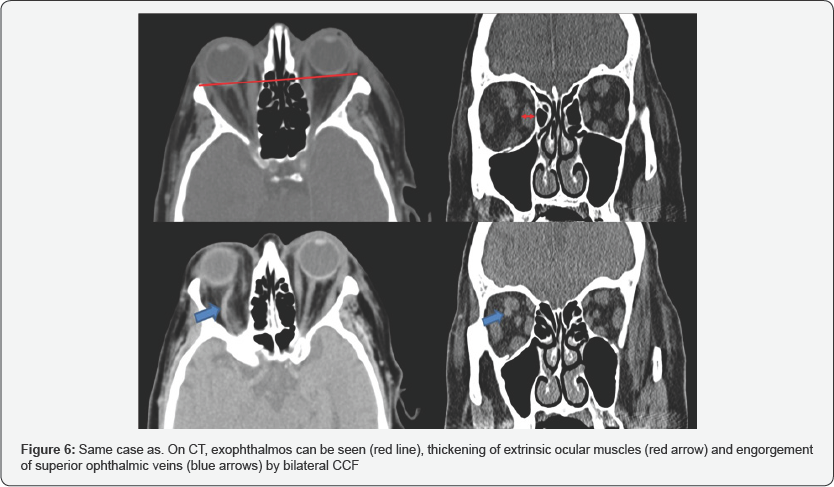

CT is usually the initial test in the CCF study. The study by helical acquisition and 3D post-processing has contributed significantly to the diagnosis of this entity. The findings that we can observe in these studies and that allow us to establish the diagnosis of CCF are fundamentally an enlarged cavernous sinus that enhances asymmetric and early with an early filling of the plexuses, venous sinuses and ophthalmic veins (Figure 5). It also allows the evaluation of orbital signs such as proptosis and thickening of the extraocular musculature (Figure 6), and in cases of direct CCF, of traumatic etiology, it allows to identify the fracture traces in the skull base [5].